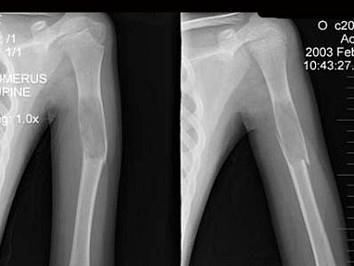

问题 13岁男性患者,因轻微外伤后感左肱骨上部疼痛,软组织肿胀,摄片见左肱骨上段局限性骨质沿髓腔膨胀性破坏,骨皮质变薄,部分骨皮质不连续,最可能的诊断是 ( )

选项 A、左肱骨巨细胞瘤伴病理性骨折 B、以上都不正确 C、左肱骨骨囊肿伴病理性骨折 D、左肱骨骨纤伴病理性骨折 E、左肱骨骨折

答案 C